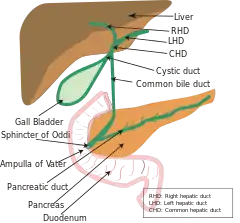

The common hepatic duct is the first part of the biliary tract. It joins the cystic duct coming from the gallbladder to form the common bile duct.

The common hepatic duct is the first part of the biliary tract.[2] It is formed by the union of the right hepatic duct (which drains bile from the right functional lobe of the liver) and the left hepatic duct (which drains bile from the left functional lobe of the liver).[3] It ends by uniting with the cystic duct (coming from the gallbladder) to form the bile duct.[4]

The duct is about 3 cm long.[5] The common hepatic duct is about 6 mm in diameter in adults, with some variation.[6]

The common hepatic duct typically unites with the cystic duct some 1-2cm superior to the duodenum and anterior to the right hepatic artery, with the cystic duct approaching the common hepatic duct from the right.[4]

The hepatic duct is part of the biliary tract that transports secretions from the liver into the intestines.